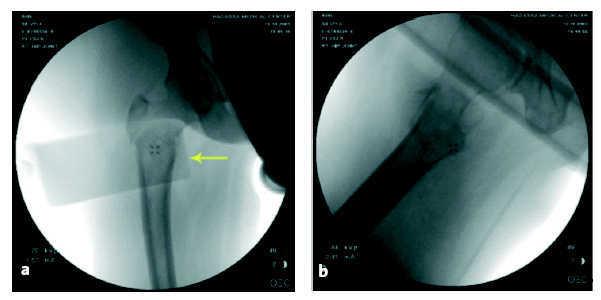

Figuras 4a y b

Imagen de intensificador de imágenes que muestra la fractura reducida en ambos planos, AP (a) y lateral (b). El rectángulo más oscuro representa el dispositivo de reducción (flecha).

Sobre la imagen del fémur proximal en el televisor colocamos plantillas de plástico para comprobar que el ángulo cérvico-diafisario es de 135º y comprobaremos que el tornillo cefálico distal se encuentra a 2-3 mm proximal al calcar femoral. Si el ángulo es inferior a 135º realizaremos más tracción.

La flecha en la imagen fluoroscópica indica el punto donde debe introducirse la aguja espinal para marcar la primera incisión.